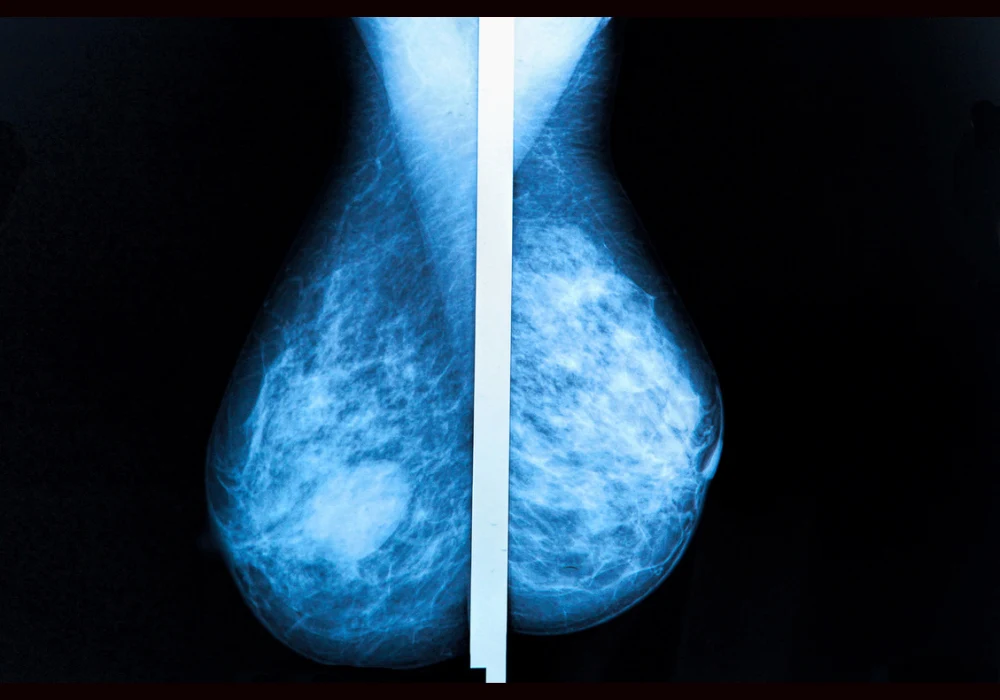

Suspicious microcalcifications are frequently detected in screening mammography, with malignancy rates ranging widely depending on imaging characteristics. The standard approach for further investigation of BI-RADS 4 microcalcifications involves stereotactic-guided vacuum-assisted breast biopsy (VABB), a reliable but invasive and costly procedure. With concerns over patient discomfort, procedural complications and healthcare costs, contrast-enhanced magnetic resonance imaging (CE-MRI) has emerged as a non-invasive alternative. CE-MRI offers the potential to reduce unnecessary biopsies while maintaining diagnostic safety. A cost-effectiveness analysis compared the two strategies to determine whether CE-MRI could viably replace routine biopsy in certain clinical scenarios.

The economic model contrasted two diagnostic pathways for women presenting with BI-RADS 4 microcalcifications: the established route of stereotactic biopsy for all cases, and an alternative approach using CE-MRI to stratify risk before proceeding to biopsy only when MRI findings remained suspicious. In the latter, lesions downgraded to BI-RADS 3 underwent imaging surveillance with mammography at 12 and 24 months.

The analysis supports CE-MRI as a viable alternative to immediate stereotactic biopsy for many women with BI-RADS 4 microcalcifications, particularly for lesions classified as BI-RADS 4a and 4b. With a high negative predictive value for invasive cancers and potential to reduce the burden of unnecessary biopsies, CE-MRI offers a patient-friendly approach aligned with modern principles of personalised care and shared decision-making.